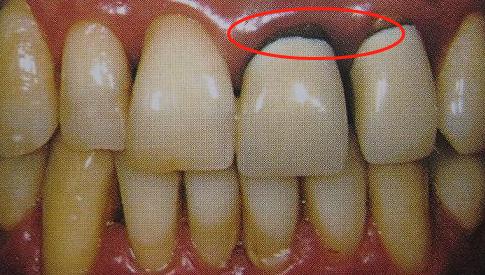

真牙的釉质和内层的牙本质都有一定的透光性,由于烤瓷牙内部的金属层是不透光的,光线在烤瓷牙的内部折射时便不能很好的到达烤瓷牙颈部,因此烤瓷牙和牙龈接触的部位相对其他部位发暗。这种发黑现象是所有金属烤瓷牙的通病。

因为烤瓷牙制备不合格,烤瓷牙和真牙不够密合,包括贵金属烤瓷牙(黄金烤瓷牙)在内,无论采用那种金属都可能出现牙龈黑线。